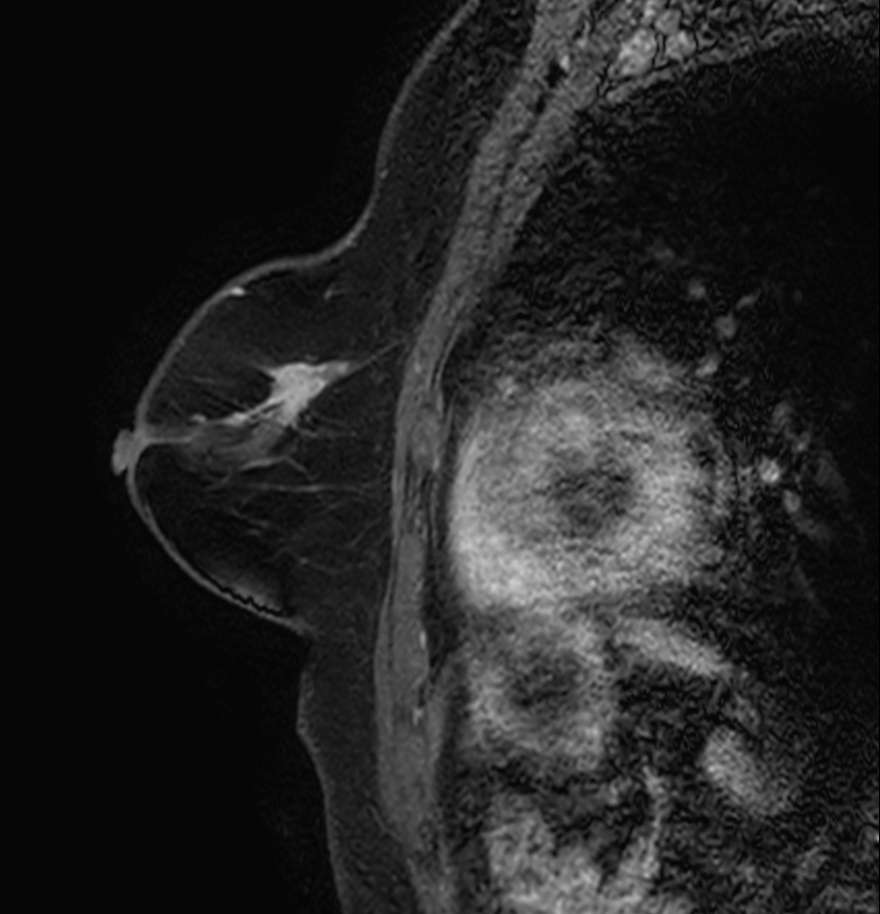

Sagittal eTHRIVE plus gado

-

Sagittal eTHRIVE plus gado (MIP)